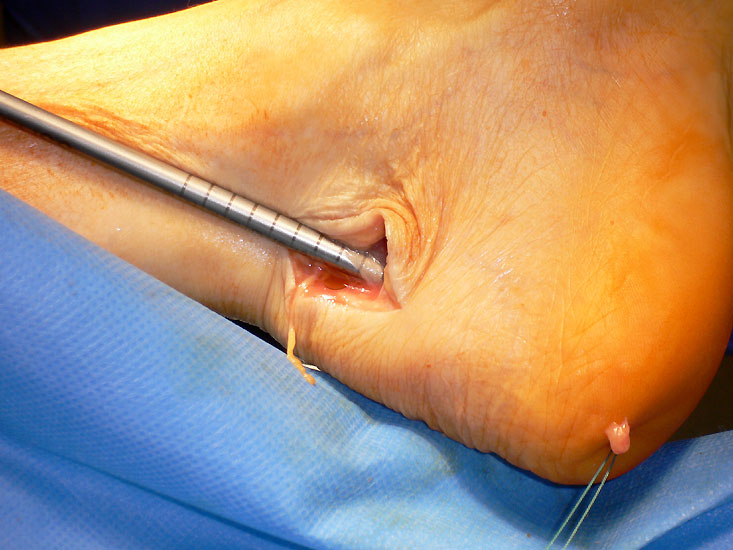

Wir mehr Sehnenmaterial benötigt, kann durch einen zusätzlichen Hautschnitt in Höhe des Chiasma flexorum die Sehne des M. flexor hallucis longus und die Sehne des M. flexor digitorum longus dargestellt werden 9. Wird ein Redonschlauch dorsal am Sprunggelenk in die Sehnenscheide des M. flexor hallucis longus geschoben, kann der Verlauf der Sehnen palpatorisch gut identifiziert werden. Diese Technik erlaubt ein Absetzen der Sehne proximal des Chiasmas über eine kleine Inzision. Beim Absetzen der Sehne des M. flexor hallucis longus ist darauf zu achten, dass sämtliche Querverbindungen der beiden Sehnen vom Stumpf abgelöst werden, damit ein problemloses herausziehen aus dem Tarsaltunnel gelingt 10. Diese Technik ermöglicht eine langes Transplantat entweder in den distalen Achillessehnenstumpf einzuflechten oder über eine Querbohrung durch den Kalkaneus zu ziehen und mit sich selbst zu vernähen (Abbildung 13)

Langer Sehnenstumpf, der über eine Querbohrung durch den Kalkaneus gezogen wurde und mit sich selbst vernäht werden kann.

Abbildung 13